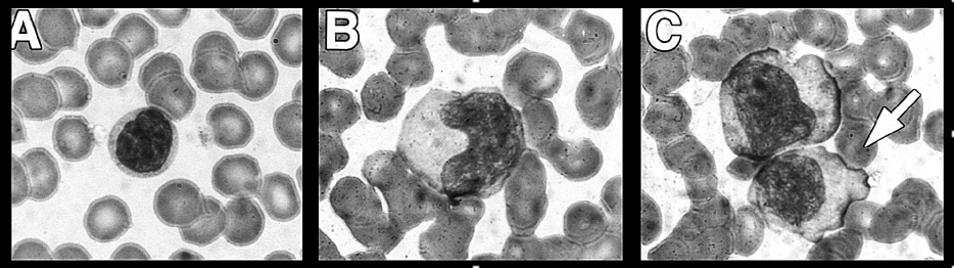

- Atypical lymphocytes [Fig] usually comprise 10-30+% of circulating lymphocytes.

Atypical Lymphocytes

A. Normal Lymphocyte

B. Enlarged, atypical lymphocyte with more cytoplasma and bilobed nucleous

C. So-called "Dutch Skirting" caused by red blood cells indenting lymphocyte outer membrane

Source: Paul G. Auwaerter, MD

Johns Hopkins ABX Guide